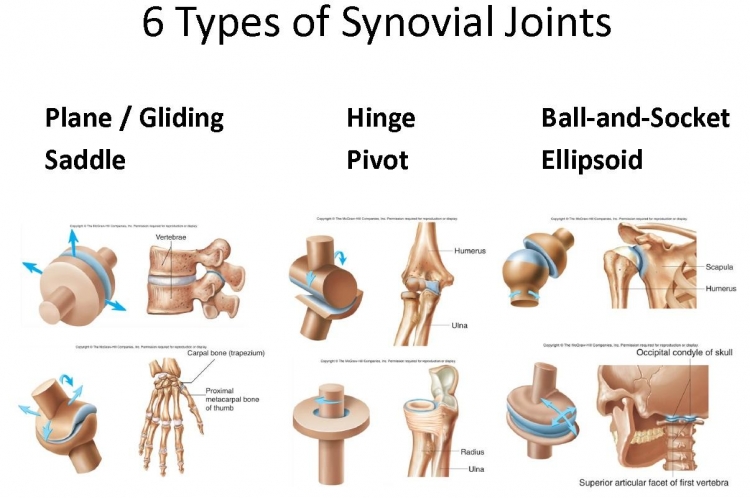

TOPIC: JOINTS

Movement in the bodies of humans is made possible by the joints in the body. The point where two bones meet is called a joint.

TYPES OF JOINTS

1. The Immovable Joints:

These joints do not allow for movement. These are:

(a) Ball and socket joint:

(b) Gliding joint:

These are found in the limbs. Ball and socket joints are in the shoulder and hip. They allow for movement in more than one plane.

2. The Moveable Joints:

(a) Hinge joint: this is a joint which allows for movement in only one plane/direction e.g. elbow joint.

Gliding joints allows the sliding, twisting or turning of one bone over another e.g. joints at the wrist.

Movement in the bodies of humans is made possible by the joints in the body. The point where two bones meet is called a joint.

TYPES OF JOINTS

1. The Immovable Joints:

These joints do not allow for movement. These are:

(a) Ball and socket joint:

(b) Gliding joint:

These are found in the limbs. Ball and socket joints are in the shoulder and hip. They allow for movement in more than one plane.

2. The Moveable Joints:

(a) Hinge joint: this is a joint which allows for movement in only one plane/direction e.g. elbow joint.

Gliding joints allows the sliding, twisting or turning of one bone over another e.g. joints at the wrist.